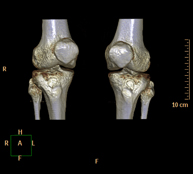

Exploració radiològica que mitjançant un sistema de raigs X i detectors que giren al voltant del pacient i que reconstrueixen les imatges per ordinador (TC Multidetector), permet l'estudi detallat dels ossos, els músculs i les articulacions del genoll. - TC de turmell-peu